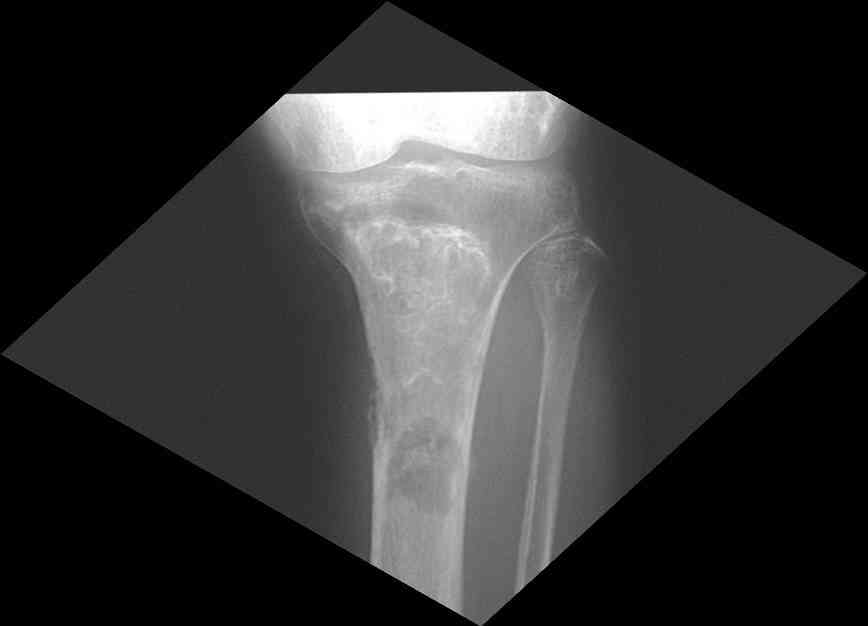

Представленные Вами данные о пациенте 57 дет с болезнью Альбертс-Шенберга чрезвычайно интересны, но диагноз вызывает большие сомнения. Для мраморной болезни характерно прееобладание склероза, а на представленных рентгенограммах преобладает симметричная дезорганизация архитектоники губчатой кости в эпиметафизарной зоне дистальных отделов бедер и голеней.

Мне кажется, представленные рентгенограммы скорее соответствуют варианту фиброзной дисплазии который был описан М. Campanacci (1976) или

обызвествляющей фиброме H.E.Schlitter (1958).

Уважаемый Константин Иванович! Полностью согласен с проф. Михайловым, данный случай не похож на мраморную болезнь, при которой имеется резкое, строго симметричное и генерализованное уплотнение костной ткани (остеопетроз), и кость оказывается построенной преимущественно из гомогенного компактного костного вещества. Для примера привожу случай из архива нашего института (бедренные, плечевые кости и таз, рис 1,2,3)

Изменения структуры костей у Вашего пациента больше похожи на полиоссальную форму фиброзной дисплазии или болезнь Педжета, возможены также инфаркты костного мозга б.берцовых костей. К сожалению, качество снимка не очень хорошее, непонятно, сохранен ли кортикальный слой б.берцовых костей по передней поверхности.

Для примера привожу случай из архива американской ассоциации рентгенологов (ACR) - развитие злокачественной фиброзной гистиоцитомы на левой б.берцовой кости у пациента с множественными инфарктами костного мозга (рис 4,5 - левая, рис 6 - правая)

Не являюсь специалистом по костной патологии, но мне кажется, на ренгенограмме множественные мета-диафизарные образования напоминяющее змееподобных извилистых линии и периостеальные ламинирование очень напоминяет картину остеонекроза (инфаркта) костей, возможно связано с длительным применением стероидов.

При предоставлении дополнительных информации, сканнирования, МРТ и лабараторных данных можно уточнить предварительный диагноз, пока склонен к обширному костному инфаркту, и таких больных рекомендуем лечить сиптоматически.

слайды из прошлегодного случая.